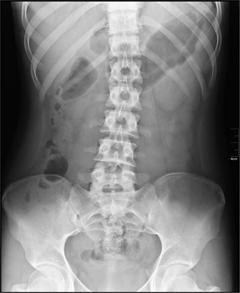

Снимки, полученные в результате рентгенографии позвоночника, позволяют определить строение и плотность костной ткани, смещение позвонков, наличие эрозий, выявить неровность контуров и участки истончения или утолщения коркового слоя костей. Данное исследование целесообразно проводить в следующих случаях:

Рентгенография позвоночника не требует никакой специальной подготовки, необходимо лишь во время исследования строго следовать инструкциям врача, принимая необходимое положение на рентгеновском столе и задерживая в определенный момент дыхание.